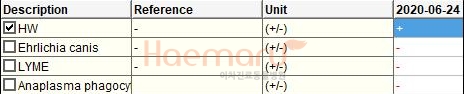

검사상 심장사상충 감염이 확인되어 사상충에 의한 폐고혈압과 우심부전, 이로 인한 흉수 및 복수 발생이 의심되는 상황이었습니다.

마이크로filaria, 우심내 심장사상충, 방사선상의 흉수 소견